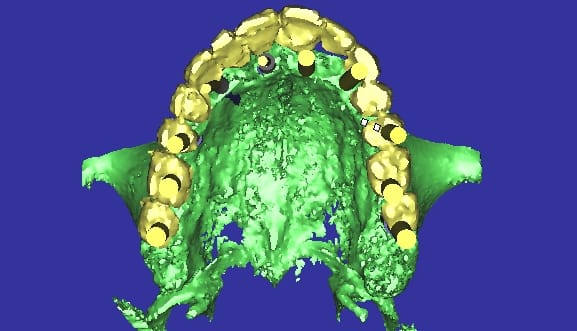

première étape;utiliser son complet pour faire dans un premier temps un guide radiologique puis deux guides chirurgicaux (je reviendras la dessus) plus tard.

pour ça c'est facile, ceux qui veulent en savoir plus n'auront qu'à demander...

essayage en bouche du guide radio.

après on envoie la patiente faire sa radio; dents serrées. c'est important!

(je reviendrais la dessus aussi plus tard)

et là on travail un peu (beaucoup) la planification.

pourquoi deux guides ?

l'un pour avoir le couloir prothétique pour les implants ne nécessitant pas de pilier conique angulé (style multi-unit), et l'autre pour pour suivre la crête osseuse (3.5 à 4 mm d'épaisseur).